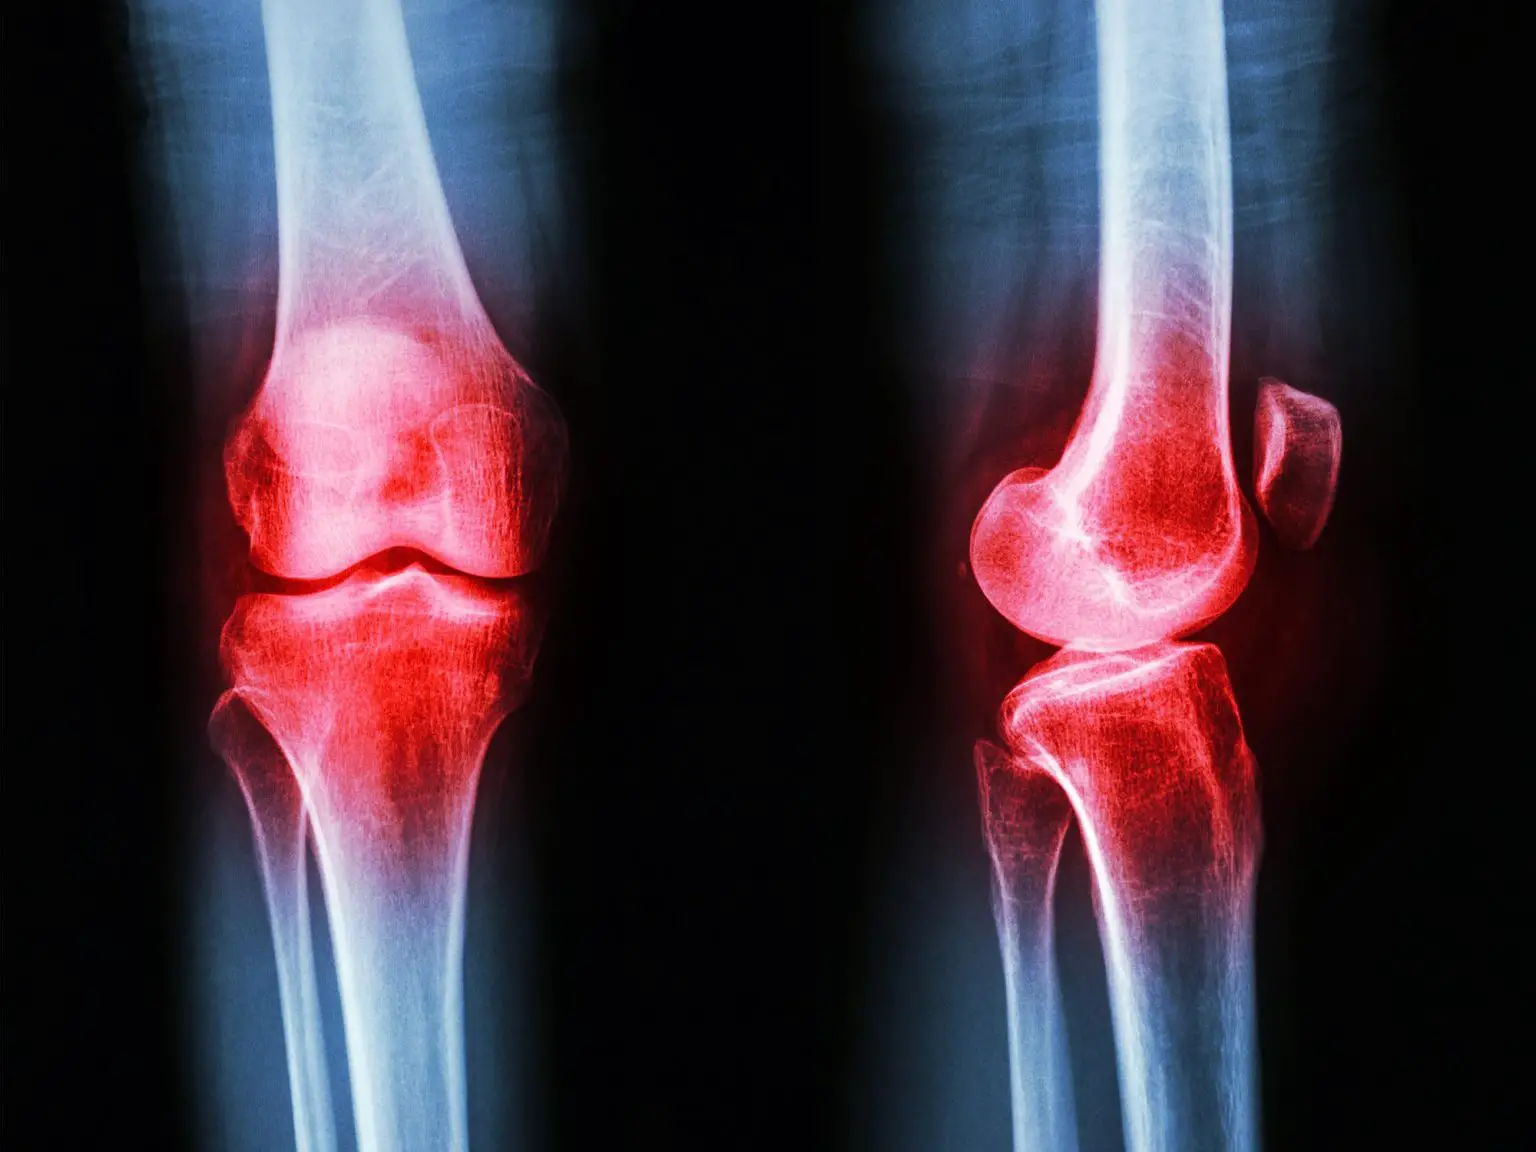

自身免疫性疾病是指人体免疫系统错误地攻击自身细胞、组织或器官的一大类健康状况。这种异常的免疫反应会导致身体各部位出现炎症和损伤。自身免疫性疾病包括类风湿性关节炎、红斑狼疮和 1 型糖尿病等。